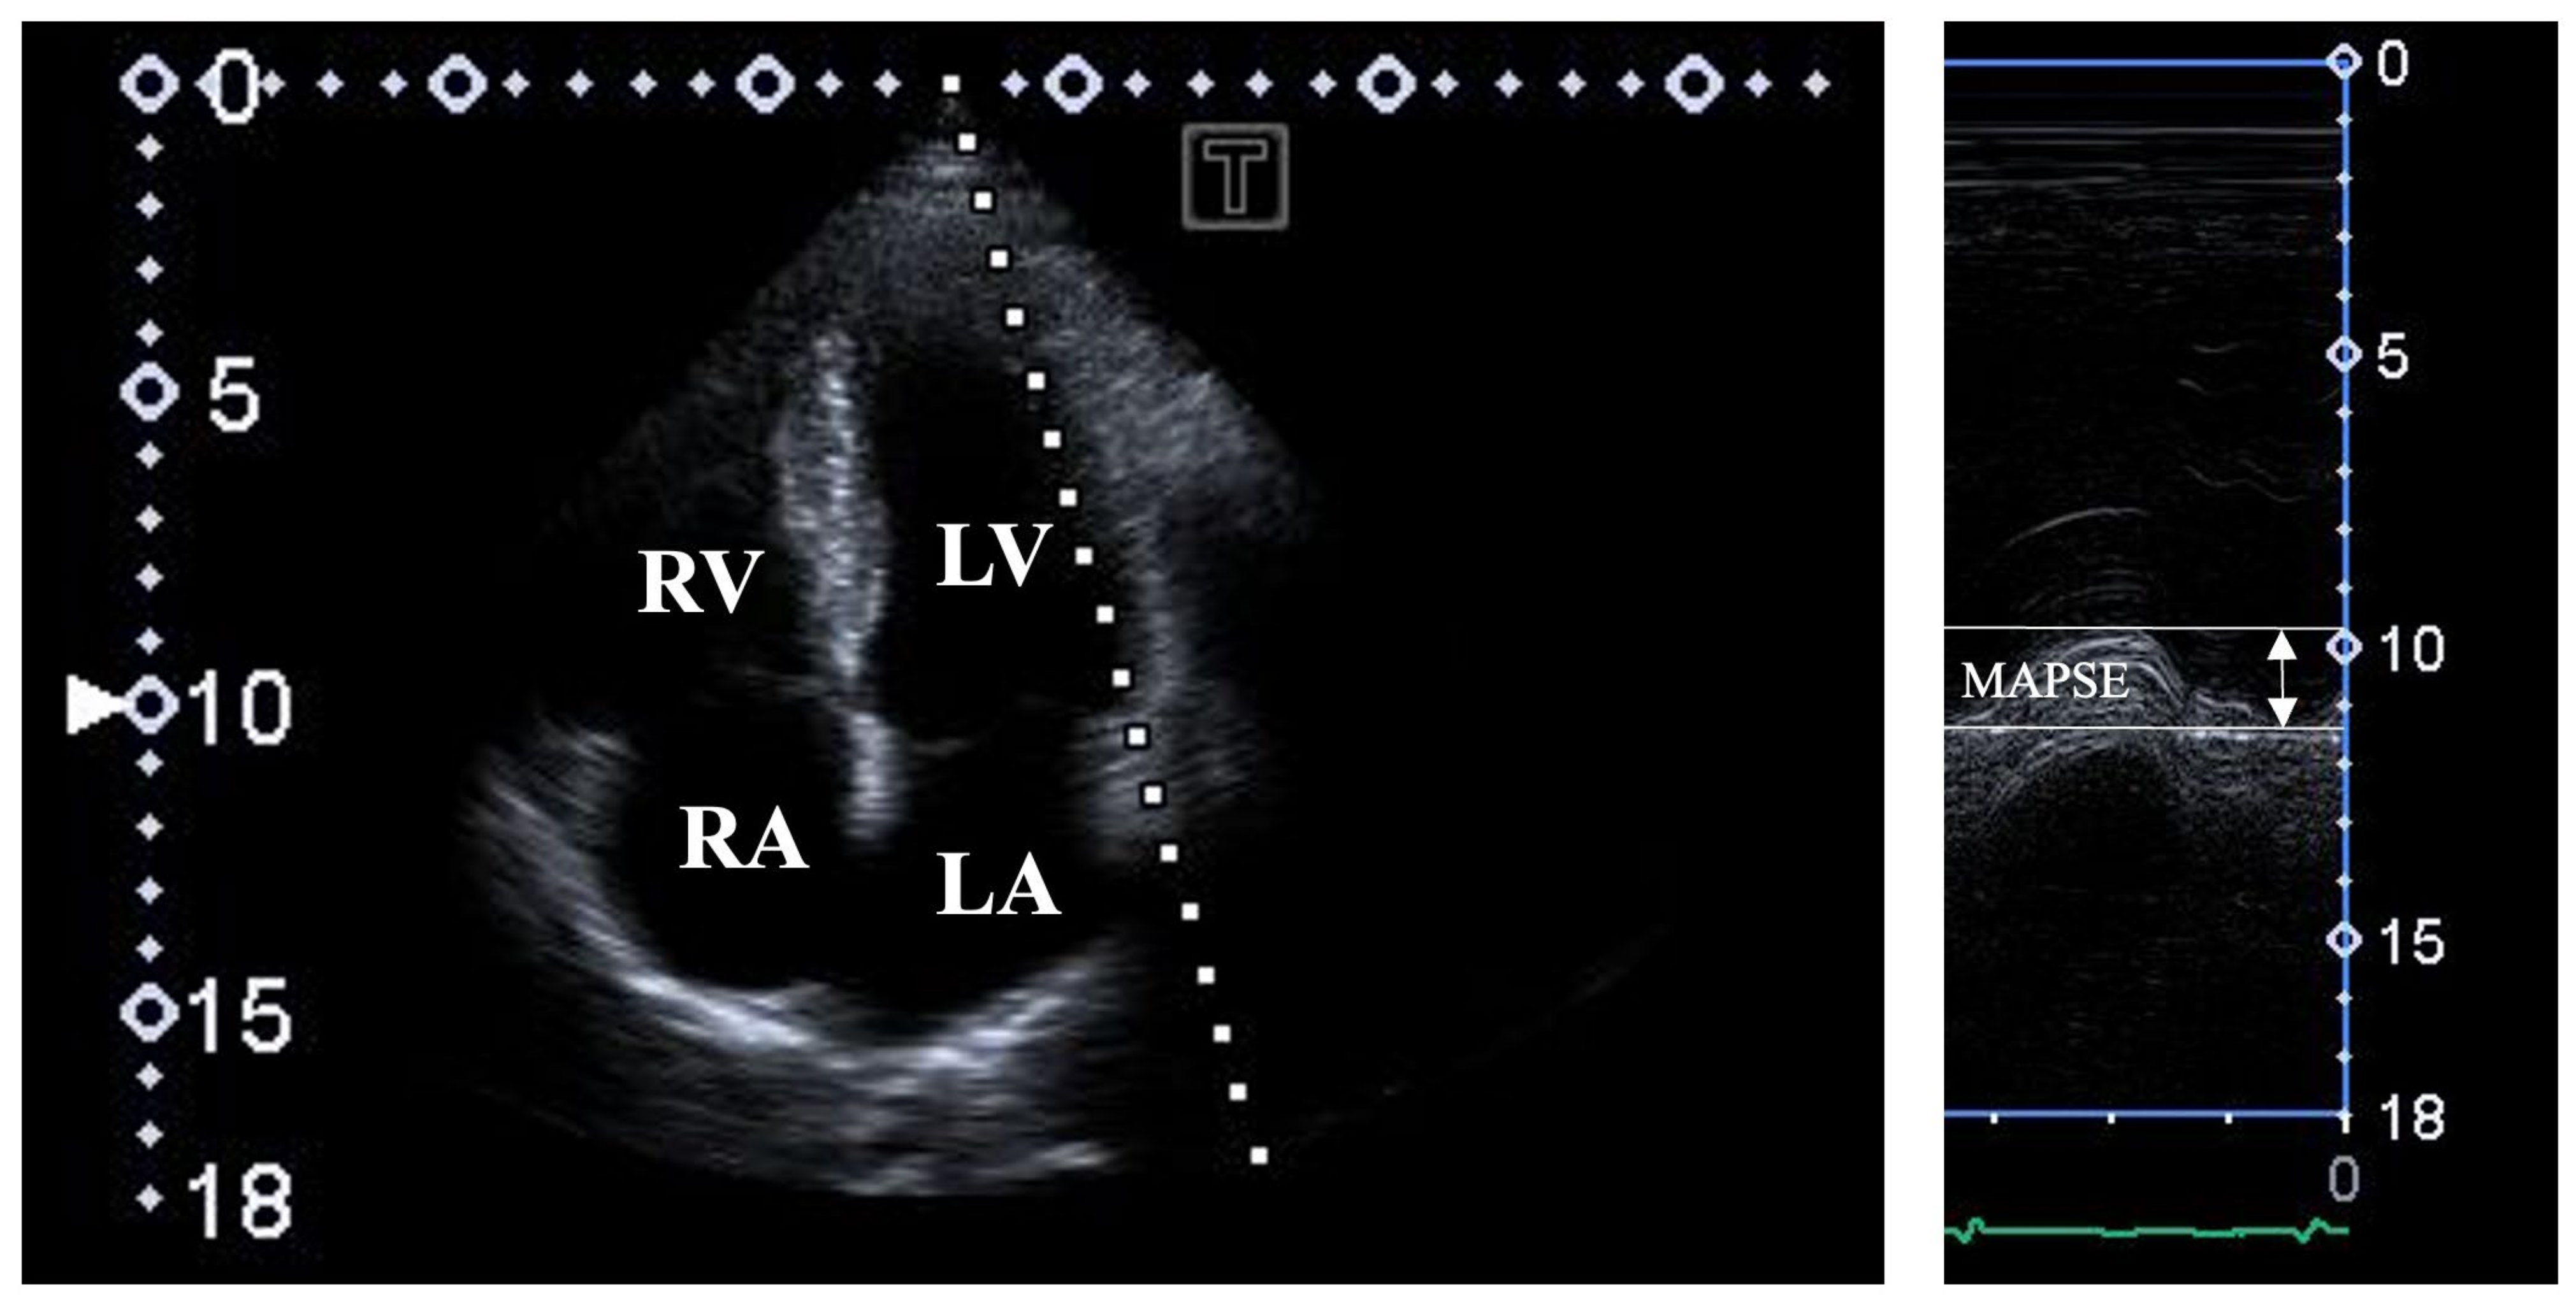

- Hensel, K.O.; Roskopf, M.; Wilke, L.; Heusch, A. Intraobserver and interobserver reproducibility of M-mode and B-mode acquired mitral annular plane systolic excursion (MAPSE) and its dependency on echocardiographic image quality in children. PLoS ONE 2018, 13, e0196614. [Google Scholar] [CrossRef]